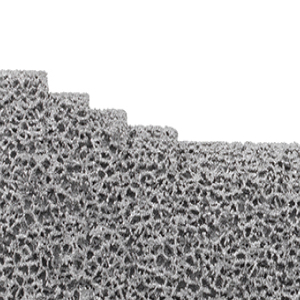

Technologie du revêtement

Le revêtement est appliqué par électrodéposition (procédé galvanique)

- Épaisseur du revêtement : 15 μm ± 5 μm

- Compatibilité : alliages de cobalt-chrome (CoCrMo) et titane (TiAl6V4)

Technologie

ChezImplantcast France, nous intégrons des évolutions technologiques dans la conception de nos implants orthopédiques, destinés à une utilisation par les chirurgiens conformément aux indications prévues. Titane en impression 3D, revêtement TiN et traitement de surface Argent pour les prothèses massives.